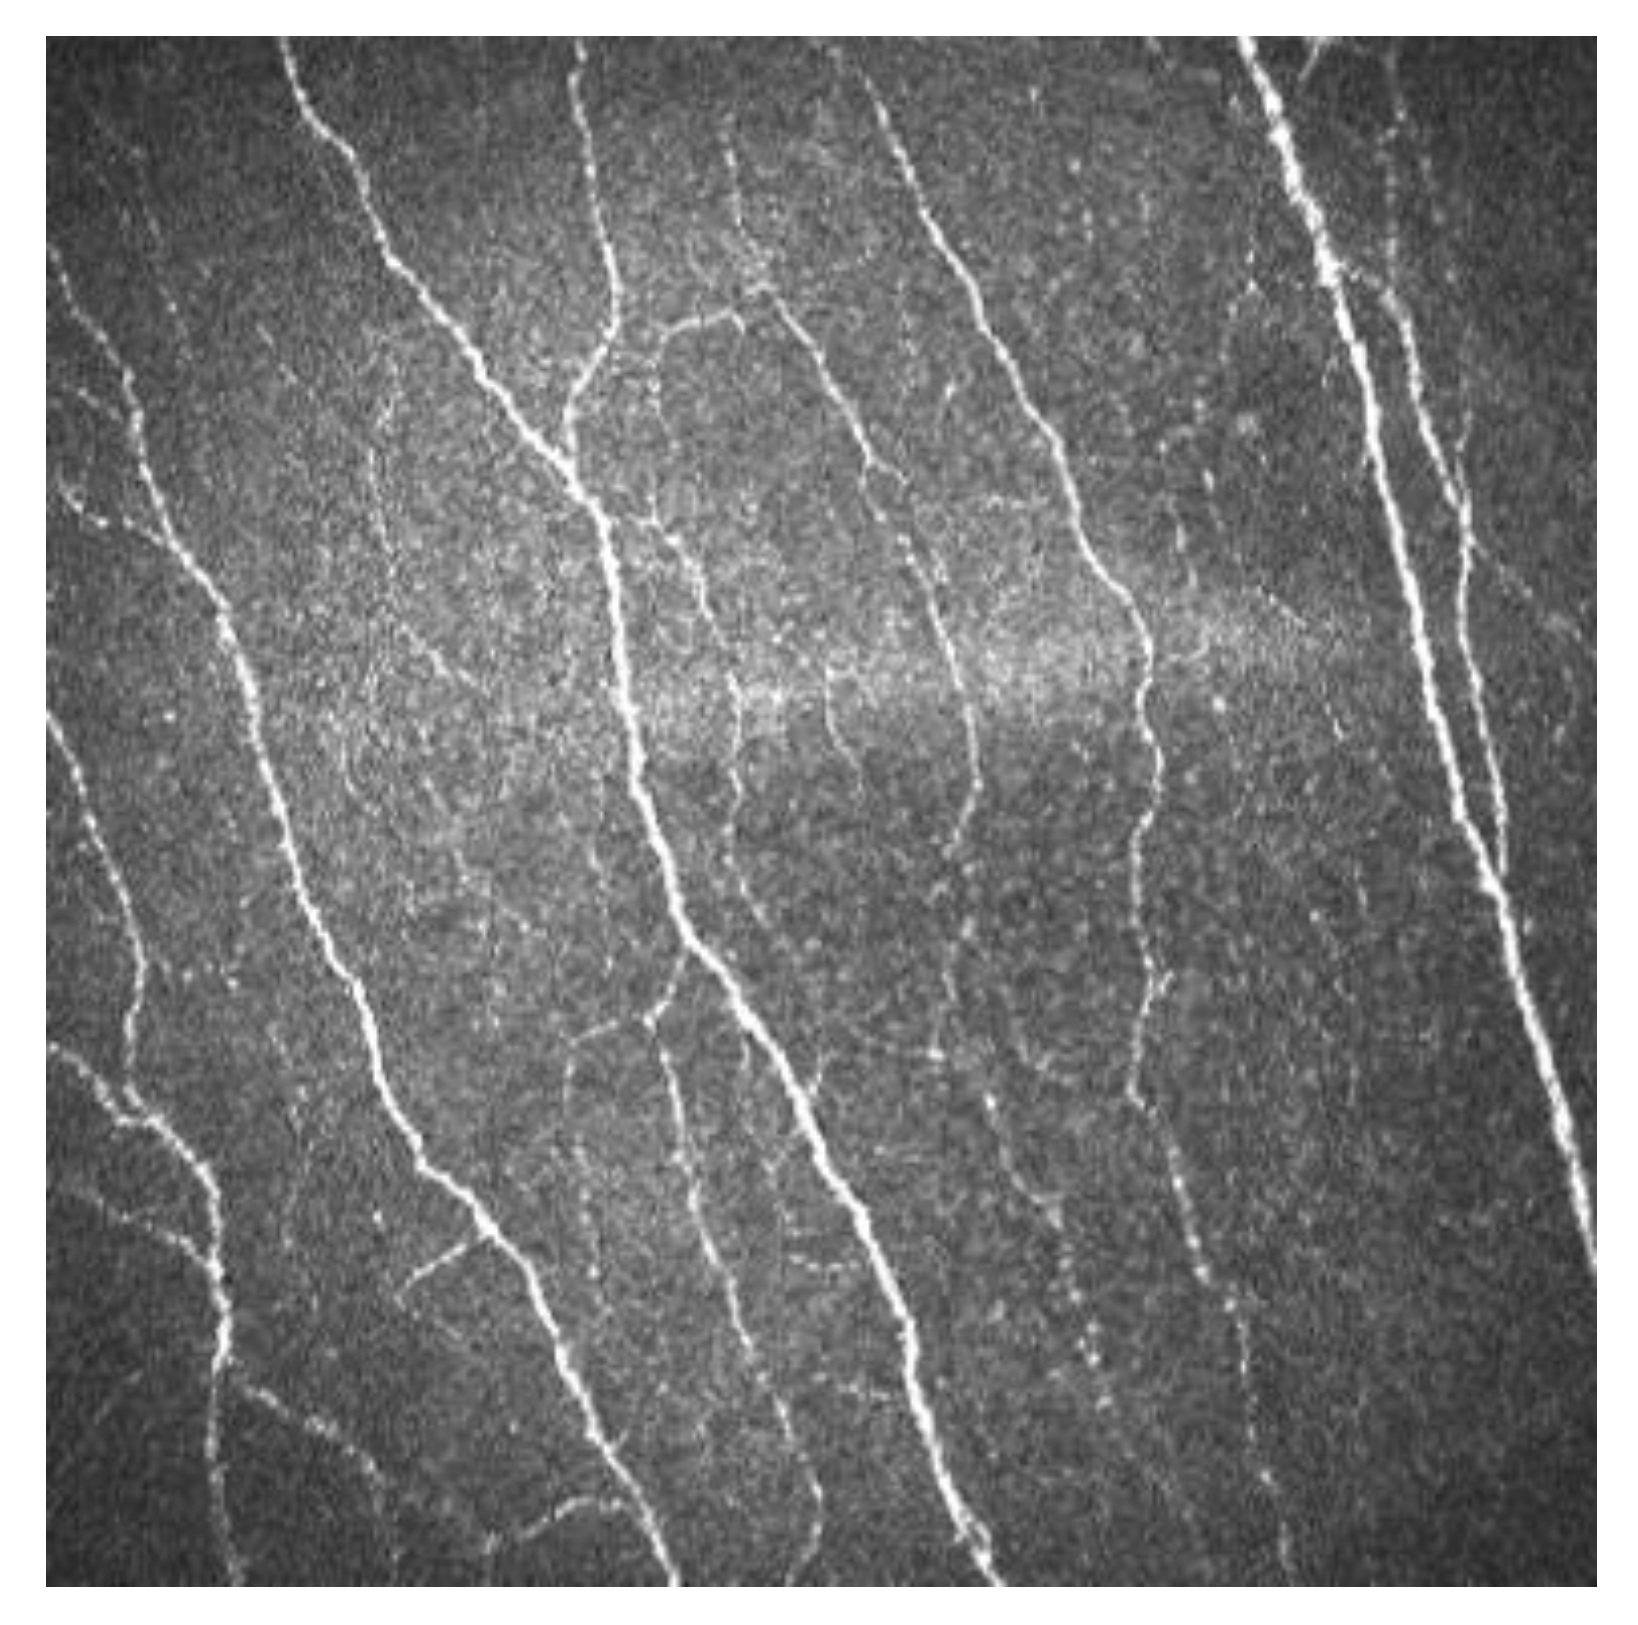

Sub-basal corneal nerves are observed as sharp white lines showing homogeneous reflectivity (Figure 2) [6,7].

Figure 2.

Sub-basal corneal nerves of a human cornea observed with corneal confocal microscopy, using the HRT II.